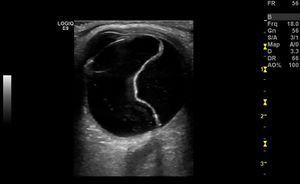

Retinal Detachment

- Echogenic undulating membrane in the posterior globe, protruding into the vitreous

- Evaluate with patient moving eye left/right

- SN 97-100% and SP 83-100%[1]